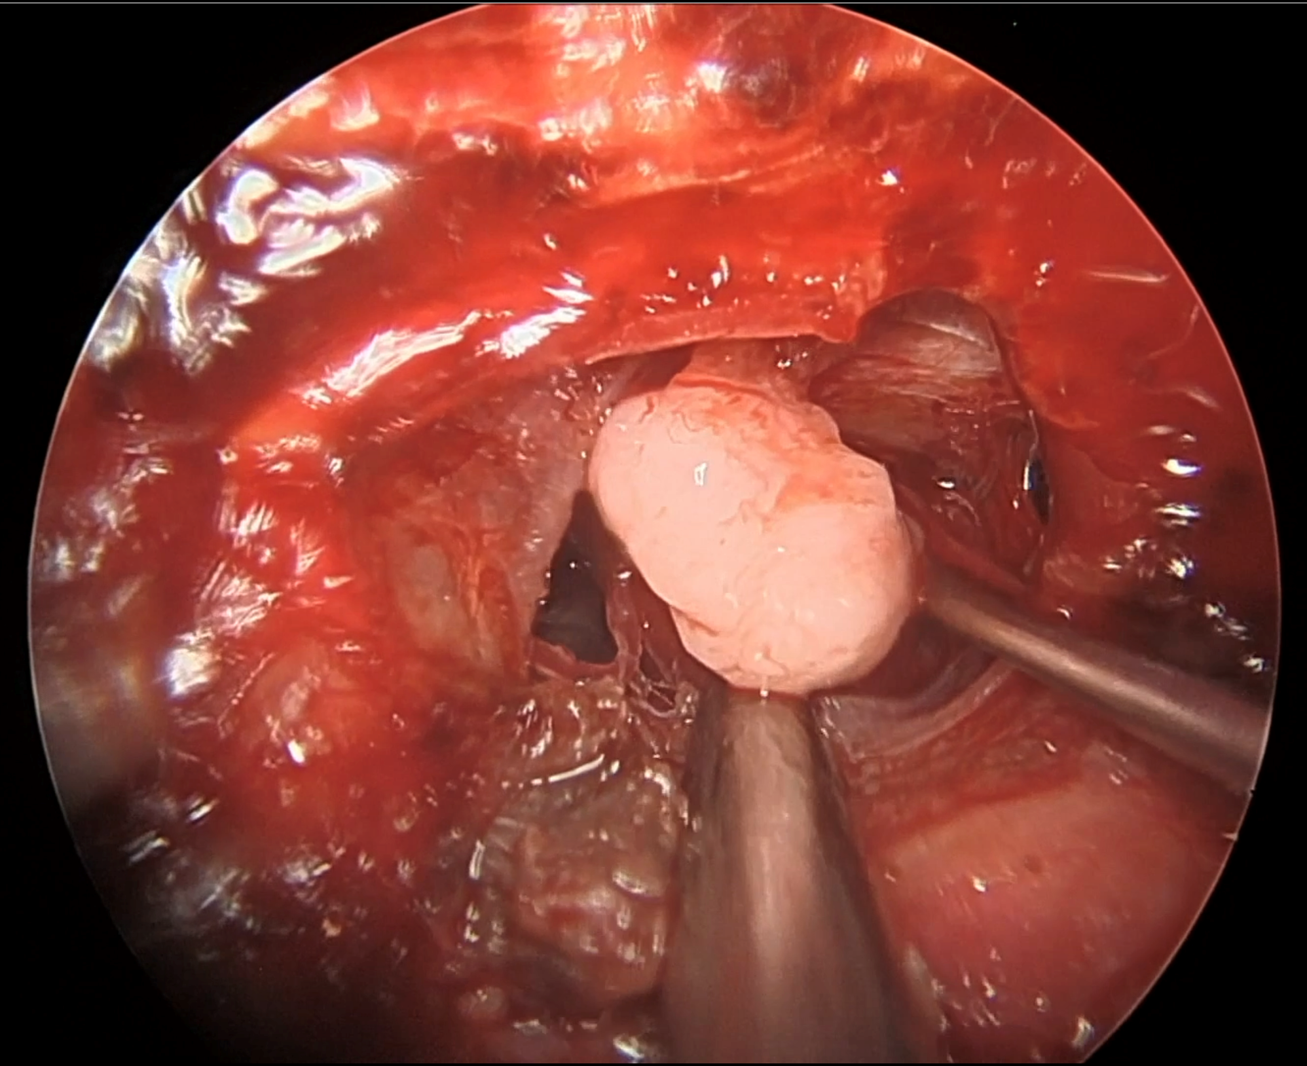

2 days after admission, she rapidly developed bilateral facial palsy. A repeated neurological exam confirmed the bilateral peripheral facial nerve palsy with marked Bell’s phenomenon and secondary dysarthria but no dysphagia. The motor exam was normal. The sensitive exam was remarkable for variable patches of pinprick hypoesthesia, non-congruent with radicular or peripheral nerve territories. Deep tendon reflexes were absent in the right lower limb, which was new. Several investigations including a brain MRI, lumbar puncture and an electrodiagnostic study were obtained.

Investigations

• CBC, Liver function, renal function, electrolytes: normal

• C-reactive protein: mildly elevated at 21.2 mg/L

• Lumbar puncture: WBC 1, RBC 44, protein 1.88 g/L; CSF culture, PCR for HSV-1, HSV-2, Listeria monocytogenes, VZV were negative

• Microbiology/Virology: PCR negative for CMV, EBV; HIV, syphilis and Lyme testing were negative

• Serum antiganglioside panel still pending

• Normal thorax CT and normal angiotensin conversion enzyme

• Normal brain MRI with contrast and normal complete spine MRI

• EMG was performed a month after symptom onset (cf. figure 1)

Evolution

Intravenous immunoglobulin (IVIg) were started at 0.4 g/kg for 5 days. Facial diplegia started resolving after the course of treatment and she was discharged with normal gait and minimal paresthesias.

Capture d e cran  le 2025 06 04 a  10.52.59

Figure 1. Electrodiagnostic study performed at 1 month since symptom onset.

Sensory nerve conductions show a decreased amplitude of the median nerve response (5.7 μV) and a distal latency increased by 3.5 in favor of demyelinating damage.